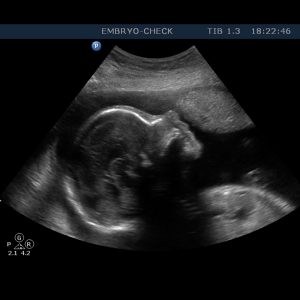

Η EMBRYOCHECK είναι εξειδικευμένη σύγχρονη μονάδα εμβρυομητρικής ιατρικής και εμβρυϊκής καρδιολογίας, αφιερωμένη στην υγεία της γυναίκας – μητέρας και του εμβρύου της και μελλοντικού παιδιού της. Ιδρύθηκε το 2006 και παρέχει υπηρεσίες που καλύπτουν όλο το φάσμα υπερηχογραφικής απεικόνισης στην μαιευτική και γυναικολογία. Βρίσκεται στο κέντρο της Αθήνας έναντι του Μεγάρου Μουσικής.